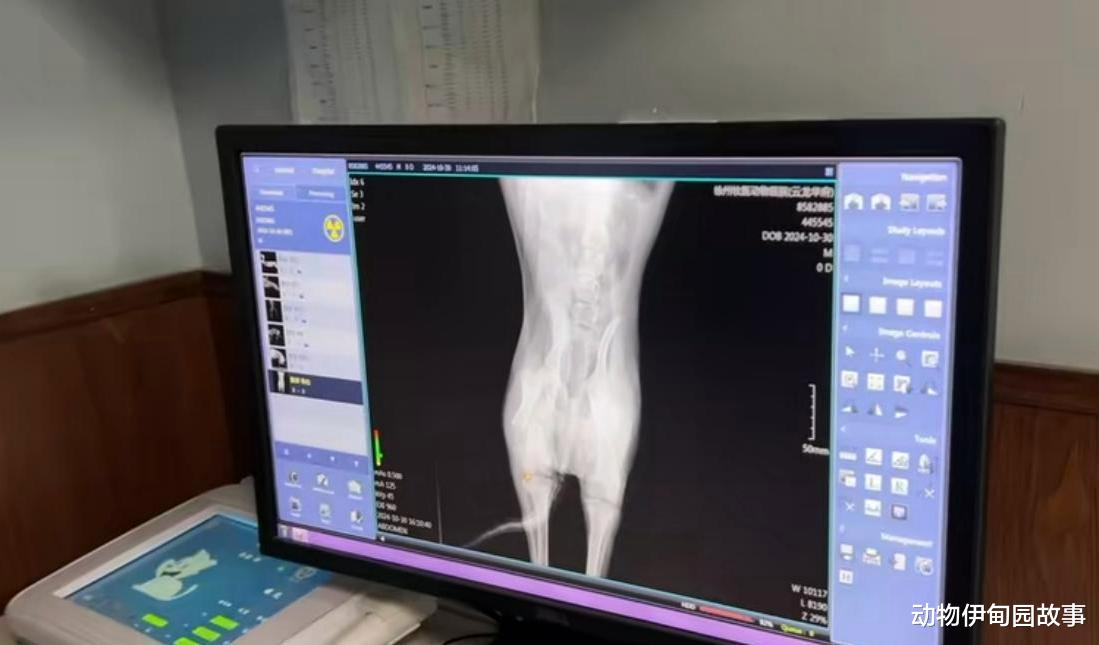

经过医生的仔细检查,发现我的腿确实断了,但无法确认我是否伤了脊椎与神经,断腿接好之后,我是否能够恢复正常,医生也不敢确定!

医生估计治疗费用六到八千,治疗时间至少得半个月。

我是幸运的,一段时间之后,我成功完成了手术,断掉的骨头都打上了钢板,只要慢慢地休养一段时间,我就能恢复了。

医生说如果我腿部神经受损了的话,想要恢复,重新站立起来是比较困难的!